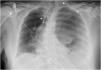

This is the case of a 67-year-old woman admitted to the ICU with refractory distributive shock. The thoracic x-ray (Fig. 1) revealed the presence of a left-sided hydropneumothorax, with a 5 cm apical pleural leave separation and contralateral mediastinal shift (⋆). The CAT scan performed (Fig. 2) revealed the presence of a hydropneumothorax and pleural empyema and periesophageal pneumomediastinum in the lower third of the esophagus (⋆). Thoracic drainage is performed, with the release of air and foul-smelling cloudy fluid containing "abundant bacteria, fat droplets, and fibers suggestive of food remnants." Upon suspicion of esophageal perforation, the new CAT scan performed with the administration of oral contrast (Fig. 3) reveals the presence of contrast extravasation at left lateral margin level of the lower esophagus, consistent with perforation, and contrast passage into the left pleural cavity (⋆). Emergency surgery is eventually performed.